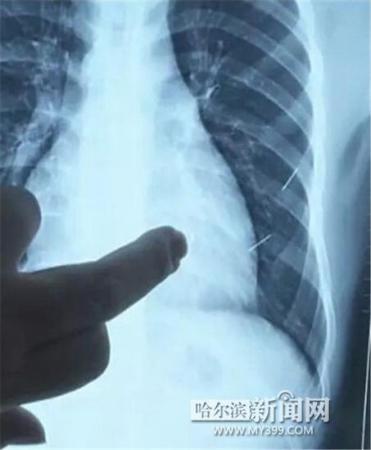

醫(yī)生指出X光片上的針狀物

昨日上午,記者在哈醫(yī)大二院第八住院部心外三病房找到了躺在病床上痛苦不堪的董立仁,家屬正在他身旁不斷安慰著他。見記者前來,董立仁母親李百燕拿出一張X光片,上面可以清晰地看到胸腔內(nèi)一共有4根針狀物,其中一根在心臟部位,兩根在胸腔壁上,還有一根在腹腔壁上。

心外三病房董立仁的主治醫(yī)生告訴記者,董立仁送到醫(yī)院時病情很危險,隨時可能危及生命?!巴ㄟ^檢查發(fā)現(xiàn),他心臟內(nèi)有一個金屬異物,正好在心臟上。心臟每次跳動都與其產(chǎn)生摩擦,導致出血,心包積液懷疑是血液。如果大量出血會凝結(jié)成血塊,血塊包裹住心臟就會影響心臟跳動,隨時都有停跳的危險。心臟上的異物是致命傷,其余胸腔壁和腹腔壁的異物傷害不大?!?/p>

昨天16時30分左右取針手術(shù)開始。因鋼針隨時會危及患者生命,此次手術(shù)定義為大型手術(shù)。開胸后,醫(yī)生打開董立仁心包,發(fā)現(xiàn)一枚鋼針已深深扎入心臟,僅露出1厘米長度在外。拔出鋼針后,醫(yī)生發(fā)現(xiàn),這枚針長達5厘米。受鋼針影響,心包出現(xiàn)大量積液,近800毫升。

隨后,在下胸壁位置,第二枚鋼針順利取出。在尋找另兩枚鋼針過程中,普外、胸外多名醫(yī)生也參與手術(shù),為主刀醫(yī)生提供更為穩(wěn)妥的處理建議。根據(jù)X光片顯示位置,醫(yī)生未在患者體內(nèi)找到剩余兩枚鋼針。醫(yī)生懷疑,其中一枚鋼針可能深藏在肋骨骨膜位置,無法尋找,最后決定結(jié)束手術(shù),做進一步觀察,研究下一次手術(shù)方案。